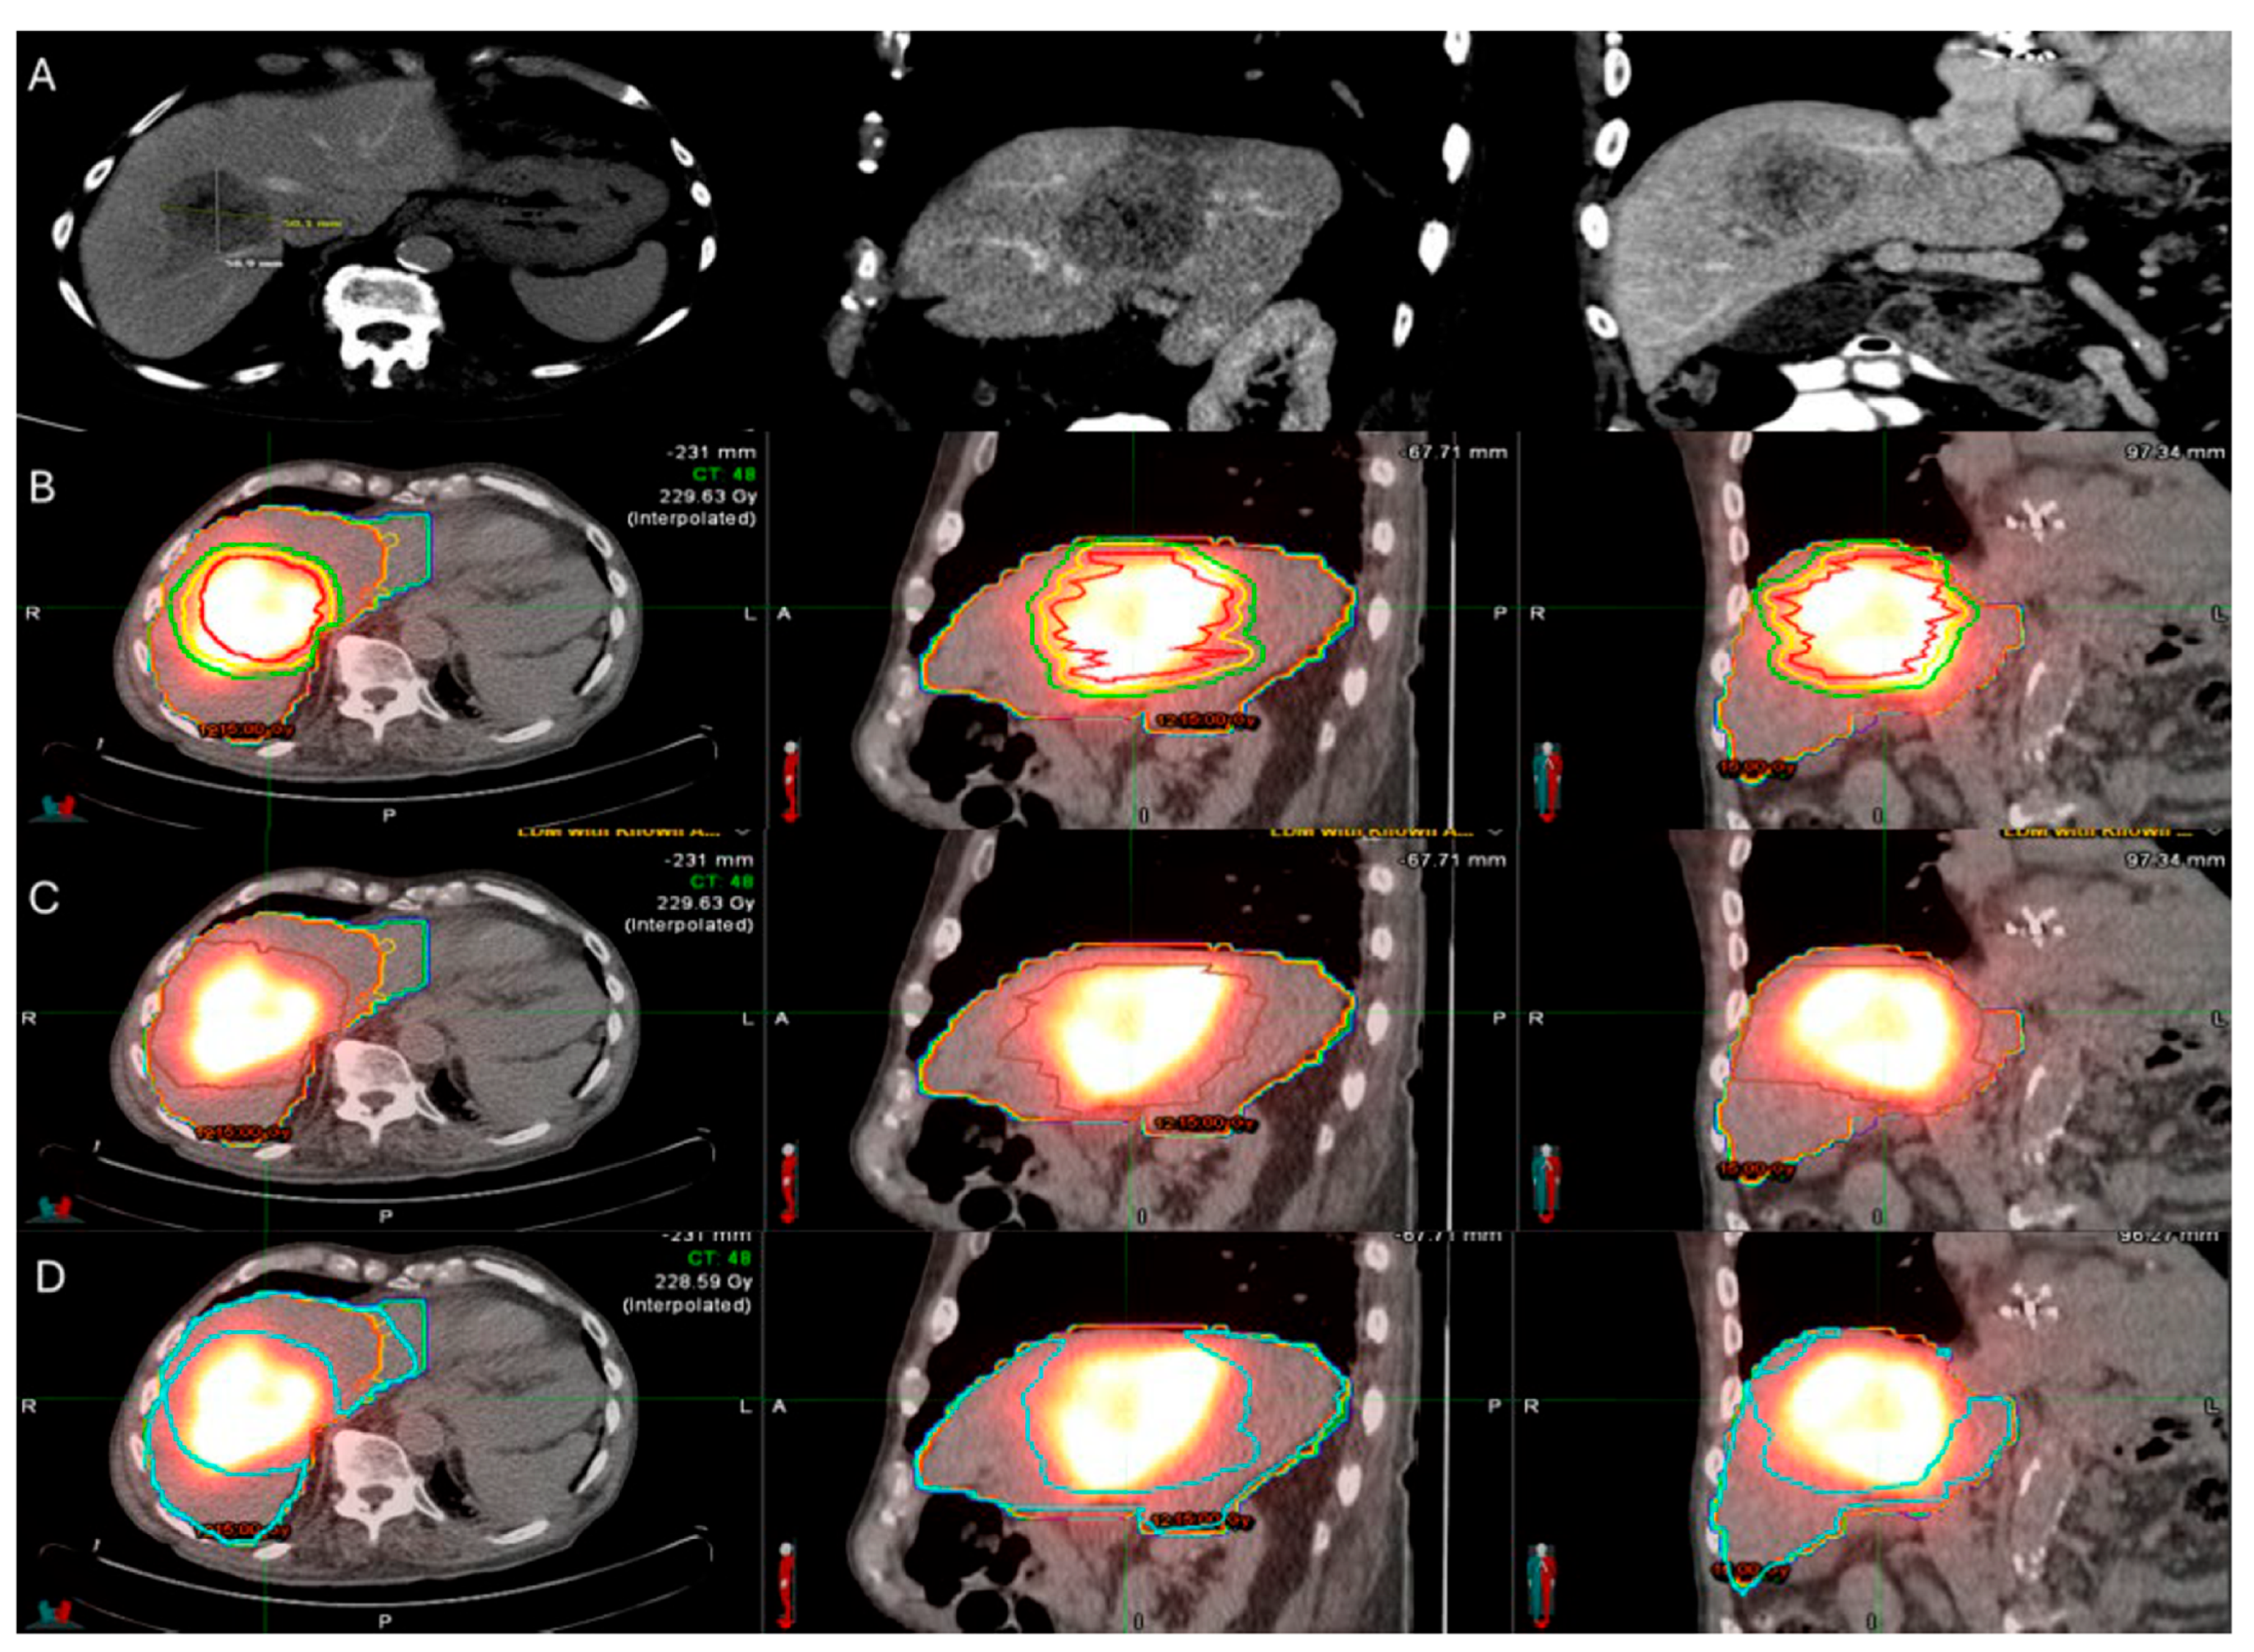

Another major limitation of TA was the lack of a reliable confirmation method of adequate uniform coverage of the target tumor by the AZ with the desired MM as depicted on cross sectional imaging [70]. In the early 2000s, there was no standardization of the MM evaluation. Ideal timing and assessment methodologies after completion of the ablation procedure were lacking. Initial assessments were based on 2-dimensional (2D) side-by-side comparisons of the pre- and the post-ablation ceCT [9,79,83,84,85,86,87]. A pivotal study evaluating the importance of the MM performed a two-dimensional assessment of the AZ and confirmed the MM constitutes an independent predictive factor of LTP after RFA. The reported reduction in LTP rate risk was 46% for each 5 mm increase in minimal margin size [70]. The authors proposed the immediate assessment of the MM intra-operatively for ablation completeness in addition to the efficacy assessment with a 4 to 8 weeks post-ablation imaging and the standardization of a reliable assessment methodology for margin verification [70]. Following studies demonstrated a statistically significant inverse relationship between LTP and MM ≥ 5 mm and no instances of LTP for tumors treated with MM ≥ 10 mm [79,88]. In KRAS mutant CLM, MM ≥ 10 mm are recommended to optimize oncologic outcomes [41,85,86,89,90]. Even for tumors with aggressive biological characteristics, achieving complete tumor ablation, characterized by sufficient margins and verified negative biopsy results from the ablation zone, remains the most significant predictor for effective local control. This comprehensive eradication significantly reduces the risk of local tumor recurrence and is considered the most vital factor in successful treatment control outcomes [91]. The literature supported that intraprocedural MM assessments have greater predictive value on LTP rates in comparison to the historic standard of 4–8 week post-ablation assessements [92,93]. Subsequent investigations indicated that volumetric 3D MM assessments are more reliable and consequently more accurate for predicting risk and location of LTP than the 2D side-by-side comparisons [13]. Specialized software systems allow pre- and post-ablation image registration and 3D evaluation of the AZ and margins (Figure 1) [70,92,93,94,95,96,97,98,99,100]. The use of biomechanical model-based deformable image registration (DIR) software (Morfeus, RayStation, RaySearch Laboratories, Stockholm, Sweden) combined with artificial intelligence autosegmentation has recently been validated as an essential method for confirming ablation completeness in hepatic tumors. A randomized phase II trial demonstrated that this approach accurately quantifies the minimal ablative margin and effectively predicts local tumor control after ablation of primary and secondary liver tumors (COVER-ALL) [101]. A statistically significant superiority in achieving MM ≥ 5 mm when they used this validation method in comparison to visual-only side-by-side AZ assessment was documented [101].

Figure 1.

56-year-old male with history of colorectal cancer under chemotherapy treatment presents with new segment 5 liver metastasis on T1 Magnetic Resonance Imaging with fat suppression (A) and fluorodeoxyglucose Positron Emission Tomography and Computer Tomography (FDG-PET/CT) (B) and undergoes microwave ablation (MWA). The target tumor is visible on the contrast enhanced Computer Tomography (ceCT) on ablation day imaging (C). Administration of the first FDG dose according to the split-dose PET/CT protocol (4 mCi), the FDG-avid tumor is clearly visualized (D). Hydrodissection is utilized to protect the adjacent ascending colon. After administration of the second FDG dose (8 mCi), the photopenic ablation zone indicates absence of residual metabolic activity (E). Ablation technical success is confirmed on post-ablation ceCT with utilization of MIM DEV software version 3.3.7. Red circle represents the tumor contours, yellow circle and green circle represent the 5 and 10 mm (mm) margins around the target tumor, respectively. The blue circle represents the contours of the ablation zone that uniformly covers the tumor with 5 mm margins, confirming technical success of thermal ablation (F). Follow-up anatomic and metabolic imaging at 2 years demonstrates involution of the ablation zone (G) with sustained local disease control (H).